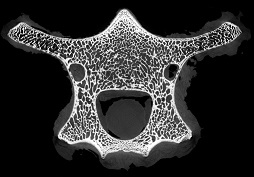

脊椎骨里的“笑臉表情包”

作者:ZZ 日期:2021-07-15 點擊數:14982次

micro CT不僅能夠獲得整體骨量的變化,還能獲得骨骼內部骨小梁骨微結構的定量指標,進而將骨小梁微結構指標、皮質骨指標及骨量結合起來,綜合評價骨強度和骨量在骨質疏松癥發生和發展中的作用。